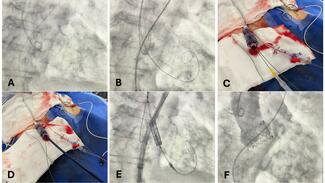

04/07/2026

Paula Vela Martín, MD; Kristian Rivera, MD; Laura Esteban Lucía, MD; Juan Francisco Oteo Domínguez, MD

A 64-year-old woman with surgical aortic valve replacement using a Mitroflow bioprosthesis (LivaNova) 9 years prior presented with prosthetic valve dysfunction. Because of elevated surgical risk, she underwent valve-in-valve transcatheter...